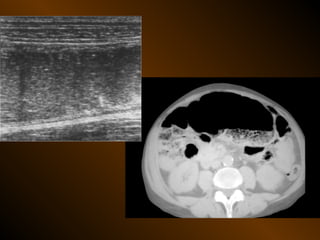

SIÊU ÂM : phụ thuộc người thực hiện

và tình trạng bệnh nhân

Kỹ thuật : chuẩn bị bệnh nhân ?

tần số đầu dò ?

Cách phân tích: dấu hiệu dương tính và âm tính

Chỉ định : linh động

SIÊU ÂM DOPPLER